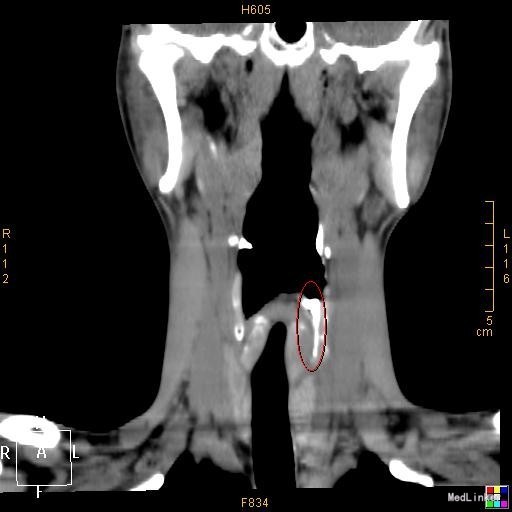

该患者在诊断上是有些困难,颈部多发脓肿是明确的,但是瘘口的位置不好确定,从而未能确诊,8年前患者行上消化道钡餐检查,诊断“食管瘘”,但是我们从8年前的影像上看,瘘口的位置太高,不像是食管的瘘口,考虑是不是梨状窝的瘘道,为了进一步确诊,我们给患者行了胃镜检查,结果胃镜发现左侧梨状窝有1个3mm大小的小孔,胃镜未能通过,食管未见明显的瘘口。为了更加明确瘘口的位置,我们与影像科商议后决定口服造影剂后行颈部CT平扫,因怕钡餐沉积在脓肿内不好排出,我们采用了口服碘化油。此次影像明确了瘘口的确在左侧梨状窝。最终诊断:左侧颈部多发脓肿;左侧梨状窝瘘道形成。 治疗:入院后予抗感染、禁食、营养支持等治疗,患者感染得以控制,请耳鼻咽喉科会诊后建议转科治疗。